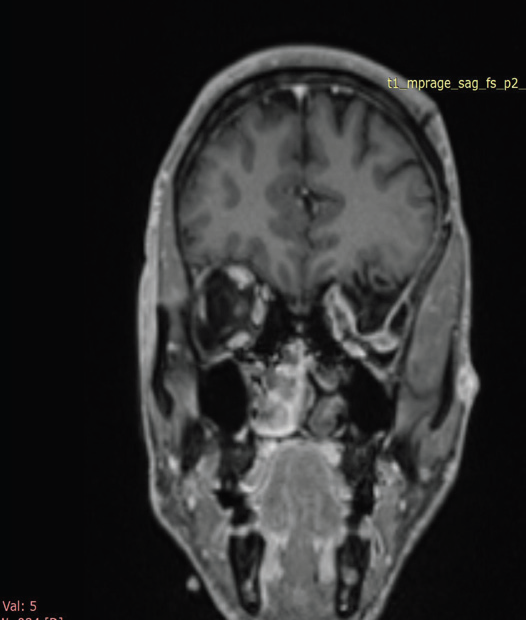

Figure 2: MRI brain, post contrast coronal T1 FS-weighted image OF

39-YEAR-OLD GENTLEMAN WITH KNOWN NF-1 demonstrates herniation

of brain parenchyma and cerebrospinal fluid into the superior aspect of the

left orbit, consistent with a left orbital encephalocele, resulting in left-sided

proptosis.

orbital encephalocele. This resulted in left-sided proptosis with

compression and mild medial deviation of the intraorbital segment

of the left optic nerve. Marked narrowing of the left superior orbital

fissure was noted, with optic nerve compression at this level.